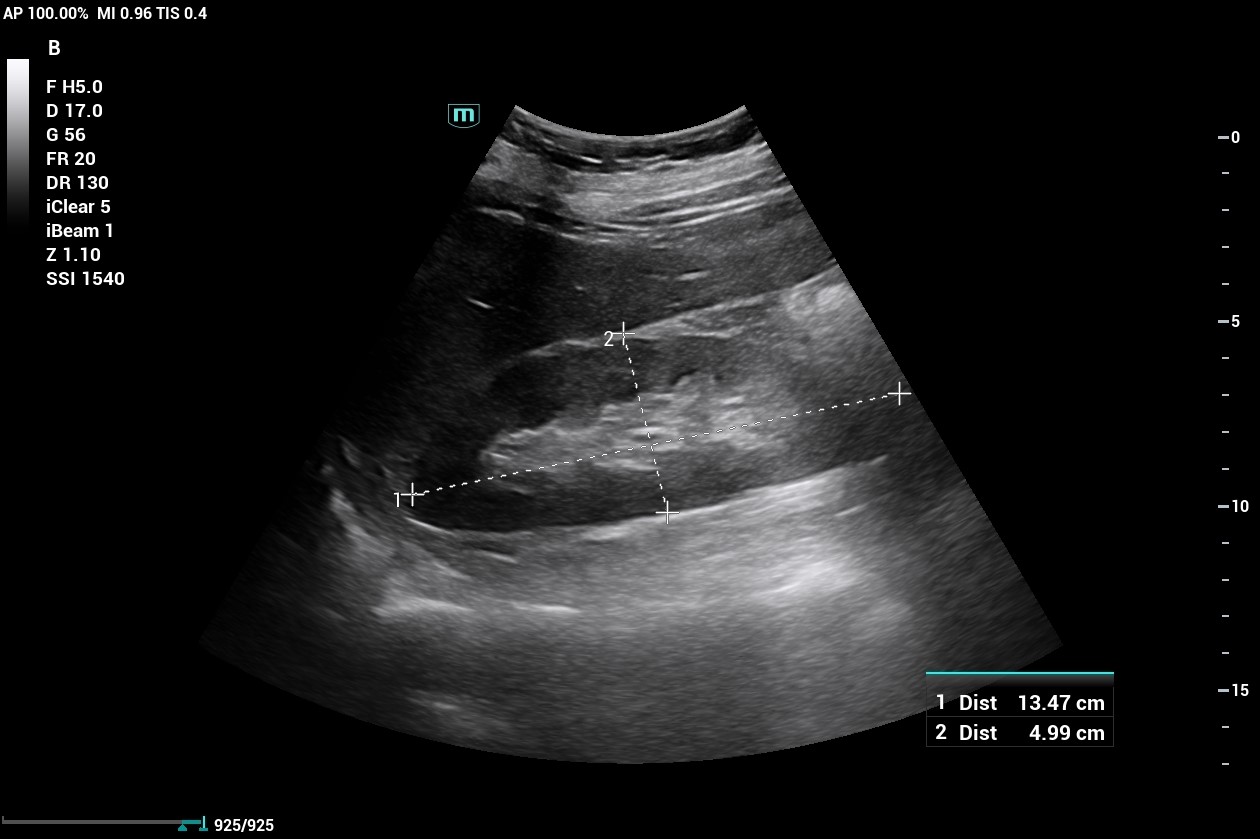

ULTRAHANG DIAGNOSZTIKA

Időpont egyeztetés a +36 30 9022 154 vagy a +36 34 473-030 telefonszámon.